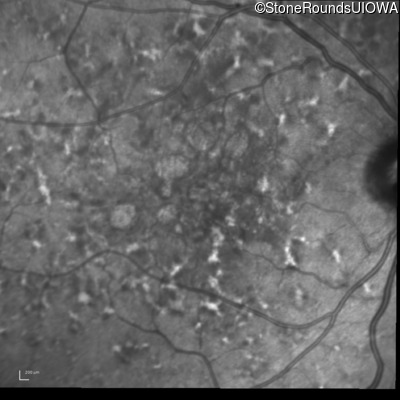

Blue Autofluorescence - Left - 20/32 sc

Exemplar